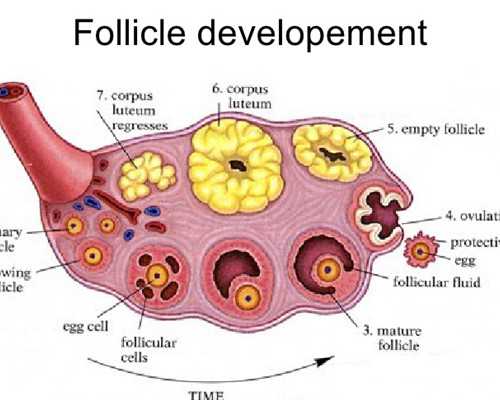

如果要談到試管嬰兒的話,可能很多人都認為這是一個比較專業的話題,其實大多數的人會發現,我們在各個不同的時間段做試管嬰兒這項手術的時候,他們也會需要各種不同的胚胎。當然在無錫人民醫院試管嬰兒手術進行過程當中,可能很多人問到的問題最多的,也就是這個關于試管嬰兒的手術情況,大家不妨一起來了解一下,我們也可以對所有的胚胎等級進行全面劃分和了解。

一級胚胎和二級胚胎

從無錫人民醫院的胚胎情況來看,一級胚胎的細胞數或者是發育的天數基本上都是合適的,那么通常情況下有7個細胞到9個細胞到9個細胞細胞的大小全部都是均勻的,而且碎片通常都是小于5%,這種情況下整個胚胎也就會有所差別,二級胚胎的細胞數和發育的天數基本上是合適的,有6個細胞到10個細胞細胞的大小全部都可以忽略不計,碎片在5%~20%之間。

三級胚胎和4級胚胎

我們在選擇做試管嬰兒手術的時候,你會發現三級胚胎和四級胚胎也是有所不同的,三級胚胎的細胞數和發育的天數明顯呈現著不符合的狀態,細胞的大小明顯不均勻,碎片在21%~50%左右,如果是4級胚胎的話,細胞的數量或者是整個發育的天數也會呈現著明顯不符合,細胞的大小有著嚴重不均勻的情況,而且它們的碎片會在50%左右,所以大家在這方面一定要格外注重。

囊胚期胚胎等級如何劃分?

在人民醫院選擇做試管嬰兒這項手術的時候,在囊胚期間如果要對所有的等級進行劃分,那么這種情況下采用的全部都是人類囊胚分級系統,也就是說可以從整個囊胚的擴張程度來進行了解,有各種不同的細胞團來進行滋養,而且要在各個不同的方面進行評價,整個囊胚腔的擴張程度也分為很多不同的等級,等級越高也就越好,對于三級以上的囊胚,那么后期會有各種不同的字母,分別代表著內部的細胞團或者是滋養層的等級。